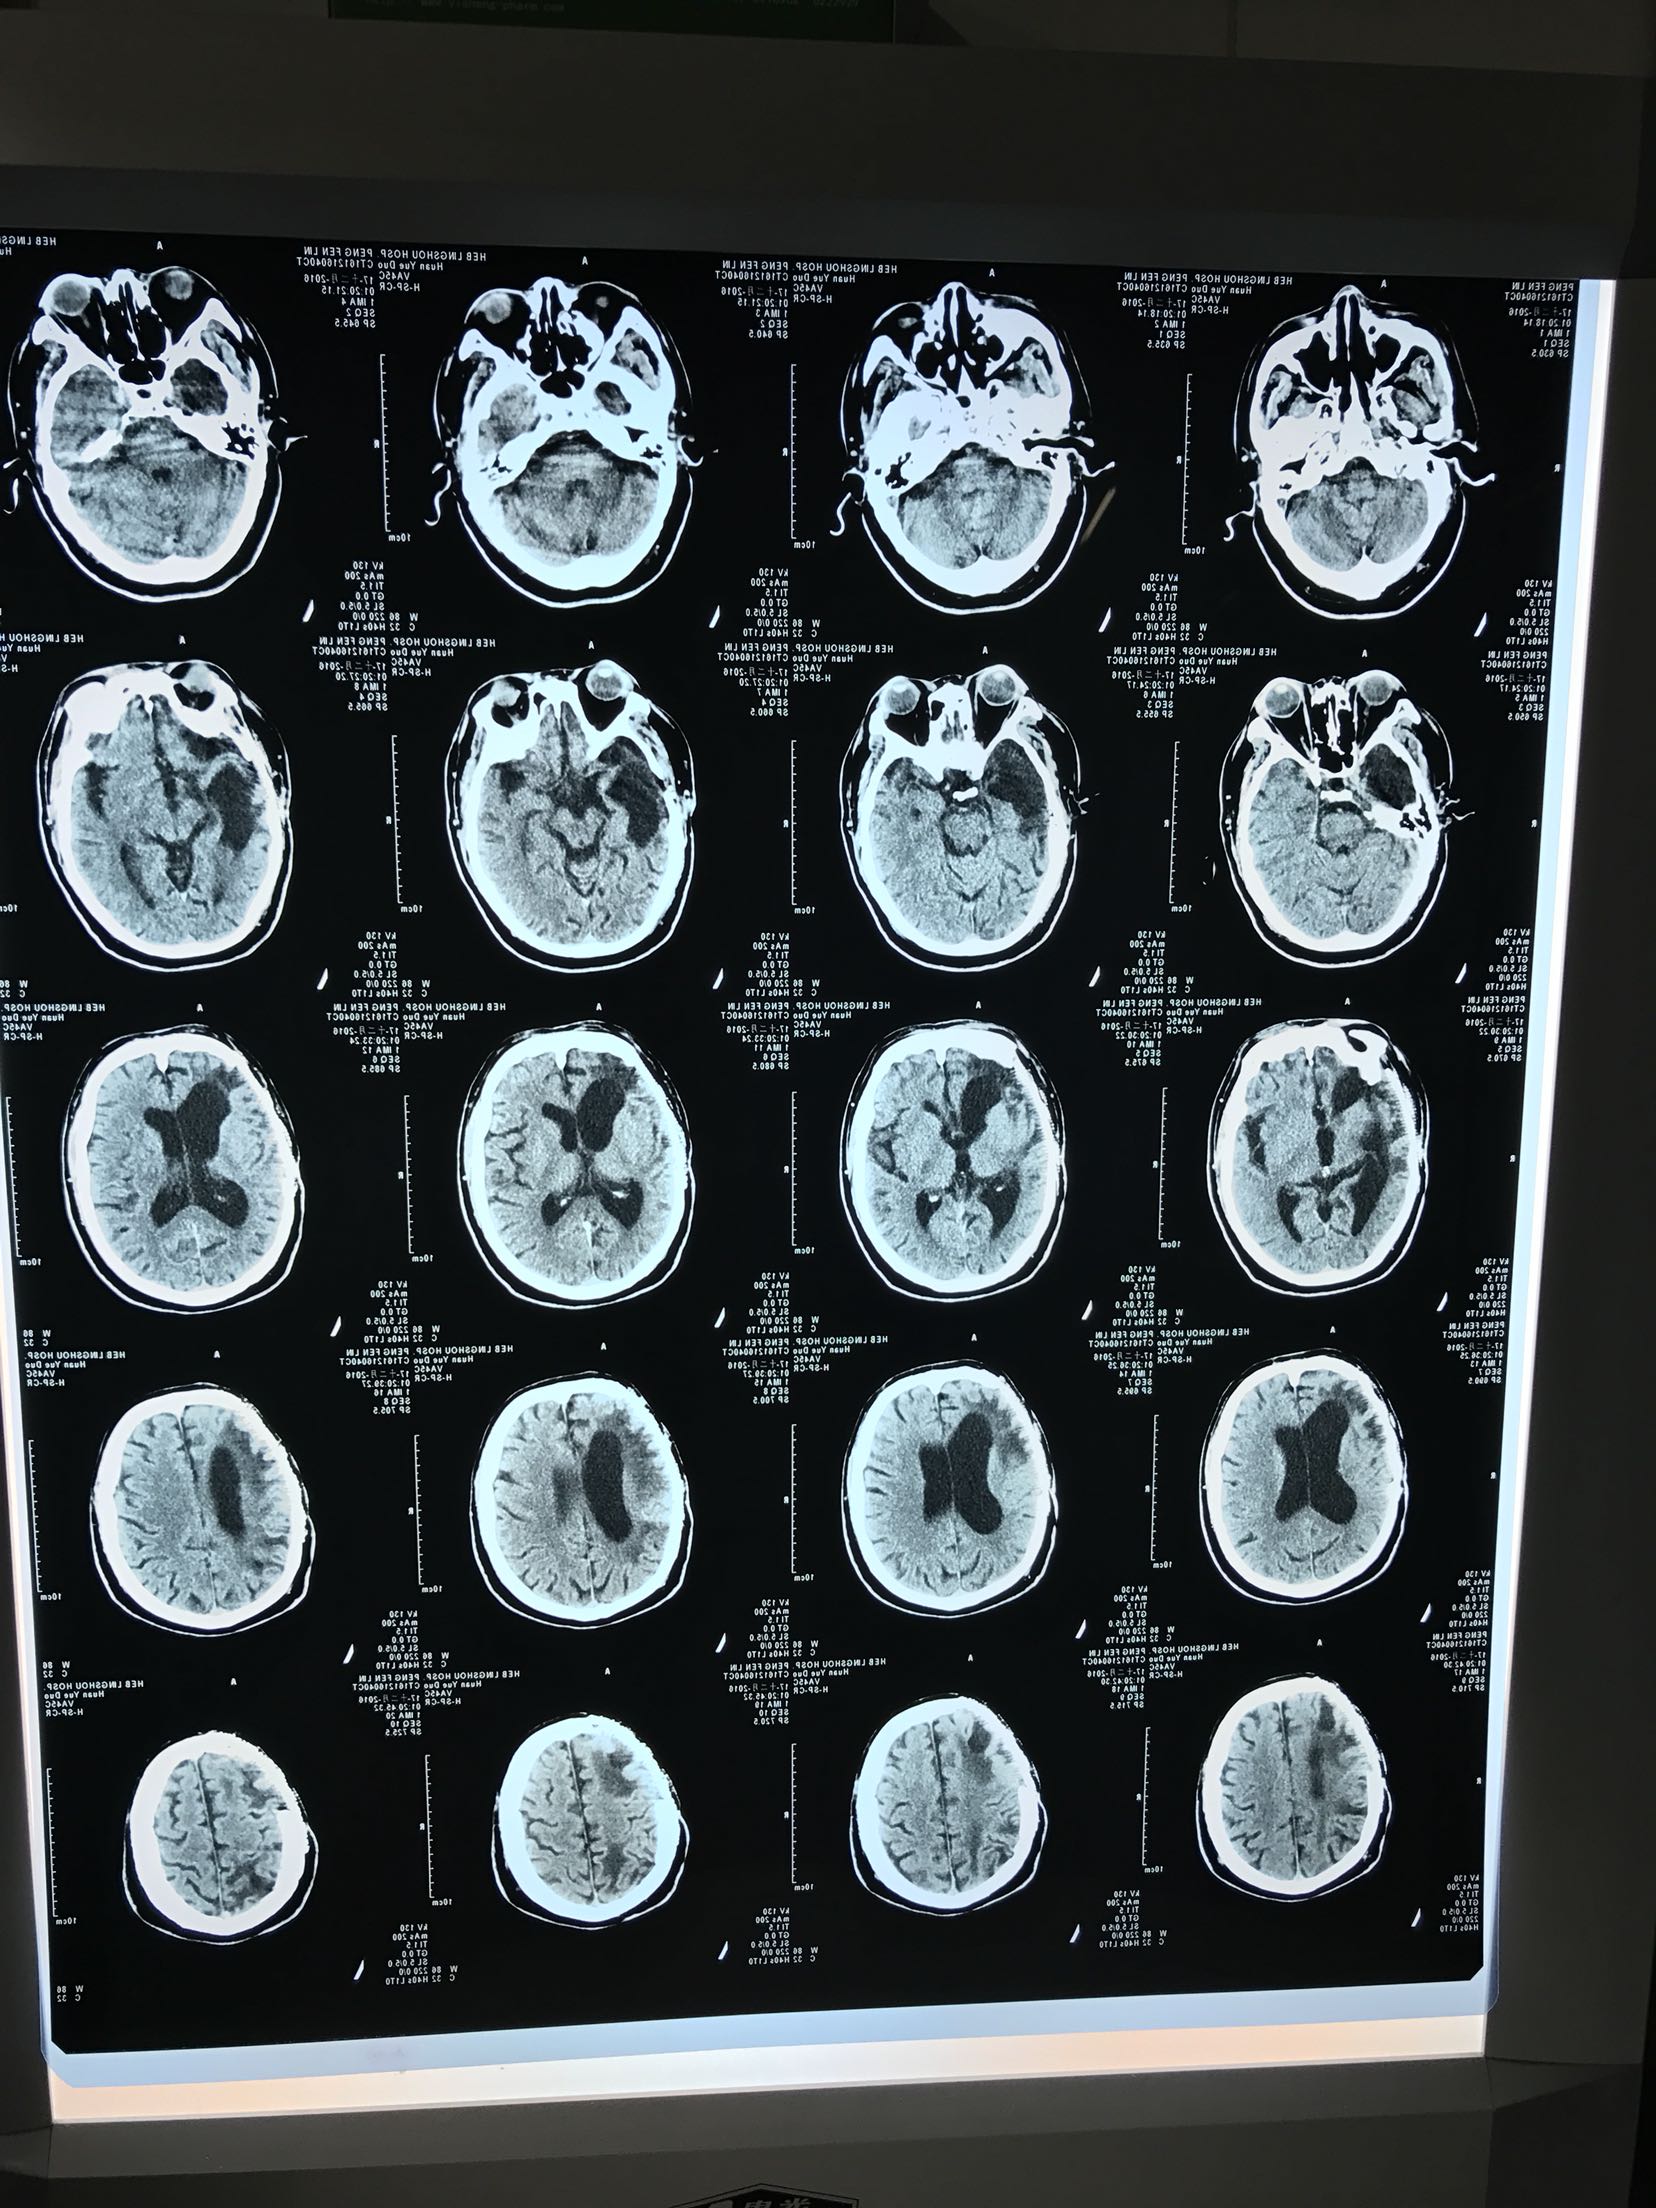

抽搐后意识不清约1.5小时,患者中年男性,既往脑外伤病史,术后遗留癫痫发作,平素口服奥卡西平,未有其他病史。患者源于入院前1.5小时,睡眠中突发抽搐,伴小便失禁,间断抽搐两次,每次持续10分钟,急打120接入我院。急诊查头Ct:1.右侧额颞顶颅骨成型术后改变,2.右侧额颞顶部软化灶伴右侧脑室扩张,为进一步治疗收住我科

T36.0℃,呼吸15次/分,脉搏102次/分,血压126/80mmhg,意识模糊,双瞳孔约5毫米,对光反射迟钝,双肺呼吸音粗,心音有力,腹无压痛,肠鸣音可,双巴氏征阴性,

颅脑外伤术后 癫痫持续状态,给于镇静抗癫痫等治疗